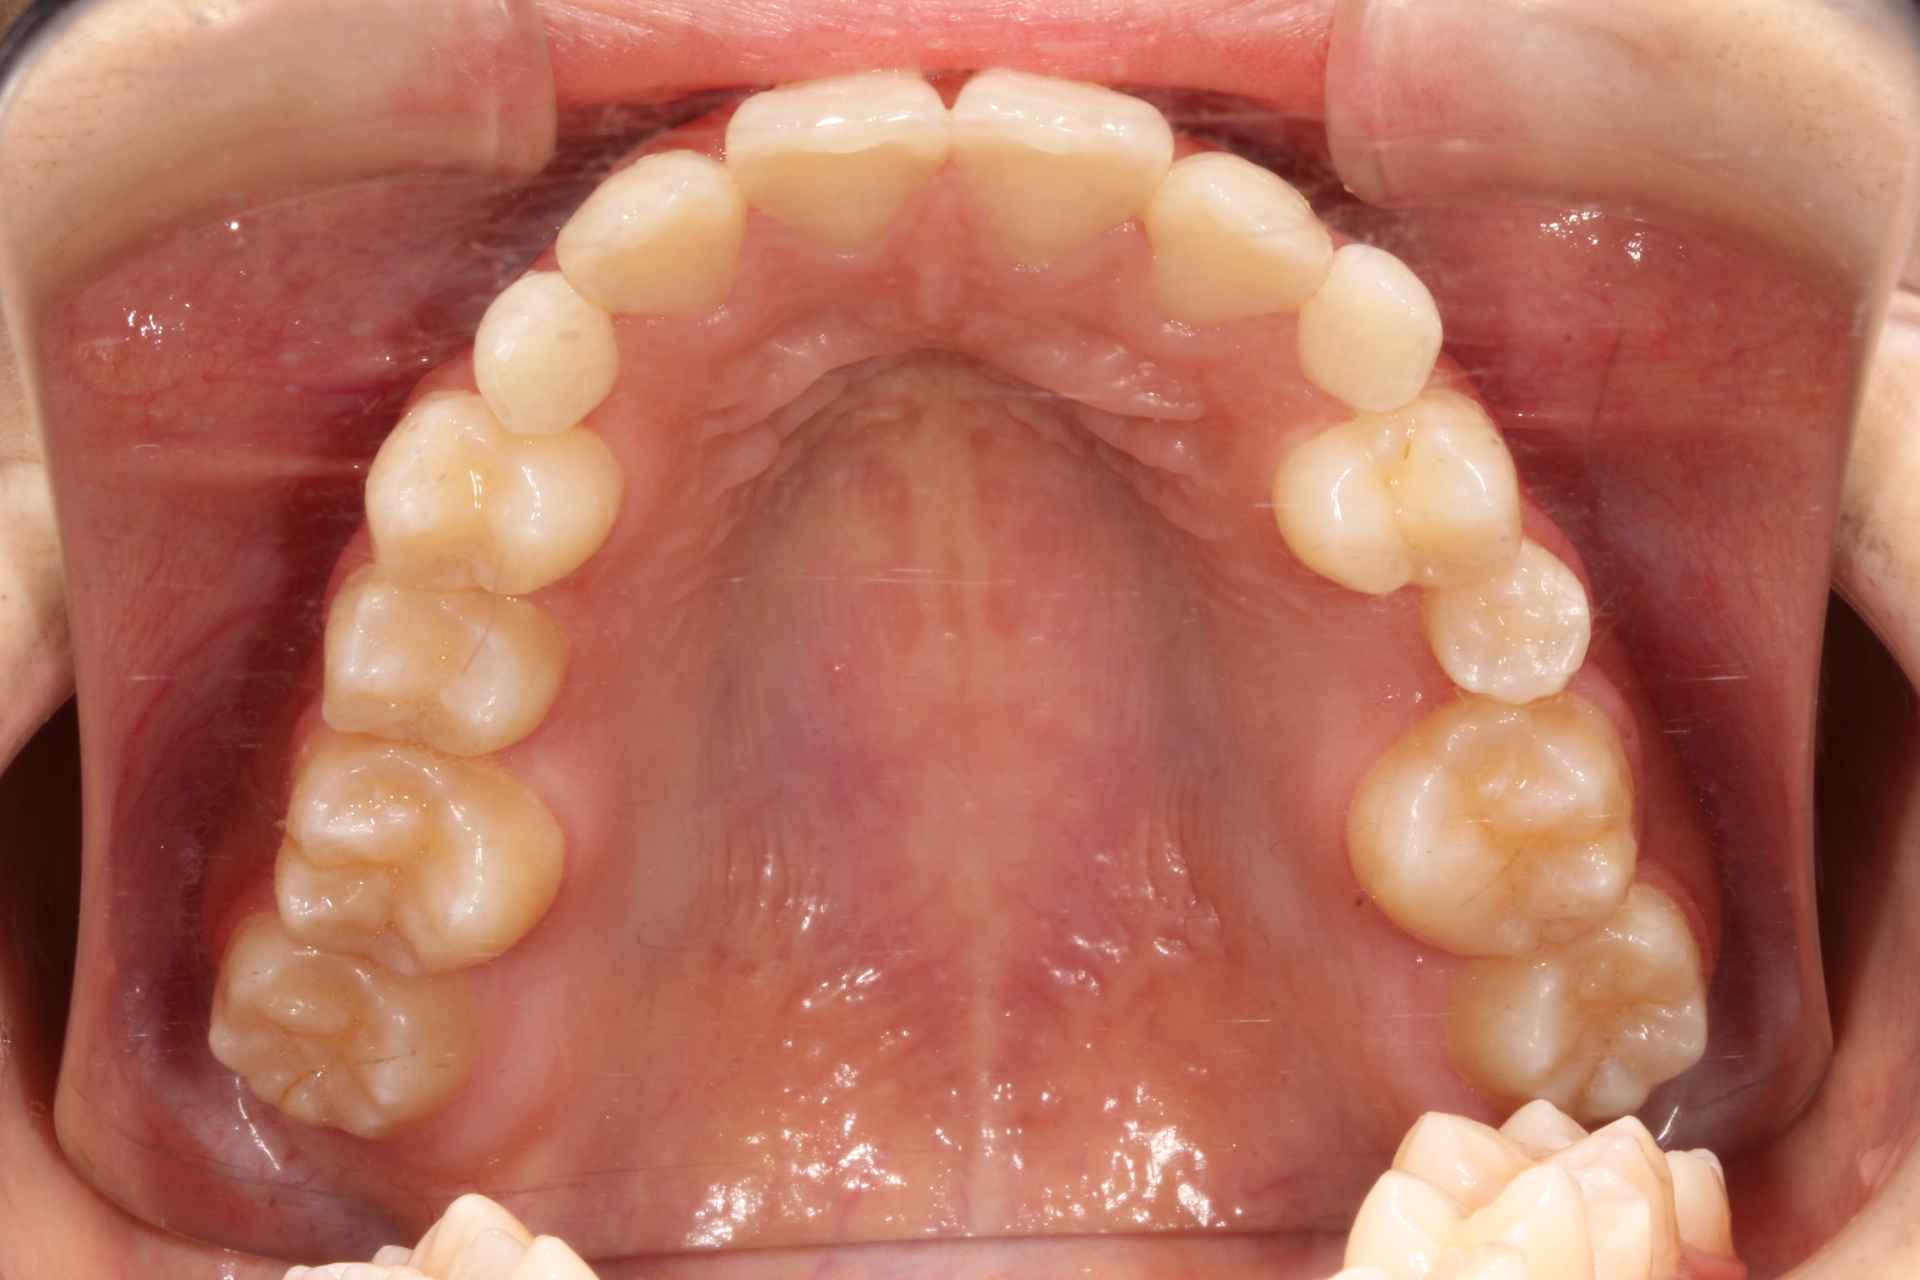

10代女性。 主訴「下アゴが出ている」。

骨格性下顎前突で本来なら外科矯正のケースであるが本人の強い希望により矯正治療のみで咬合改善を行う。

まずは前歯部の被蓋関係改善の為に、Carriere MotionとⅢ級エラスティックを使用し下顎の後退を行う。その後マルチブラケットにて永久歯咬合関係の改善を行った。